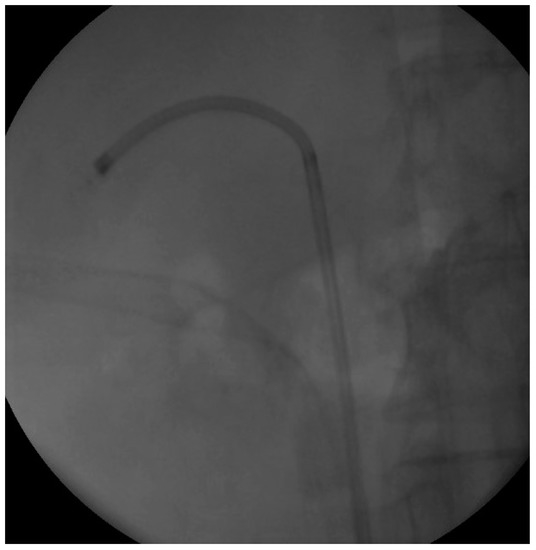

We proceeded with our standardized protocol of RIRS. Under general anesthesia, the patient was placed in the lithotomy position. At first, we performed a cystoscopy of the bladder. We found the right ureteral orifice and placed an ureteral catheter. Via the catheter, contrast agent was infused and, under fluoroscopy, the renal collecting system and the calculi was detected (Figure 1). The insertion of the guidewire followed, an ureteral access sheath was placed and through it we reached the kidney with a flexible ureteroscope of 8.6 French. The stones were found in the upper calyx and in the pelvis (Figure 2) so we began lithotripsy using holmium laser, checking throughout the whole procedure with fluoroscopy. In the meantime, the contrast agent was almost eliminated from the pelvicalyceal system and the stones were efficiently exported. Although we could not see any other calculi in the system, in the fluoroscopy there seemed to be one more (Figure 3). Therefore, we continued our endoscopy in order to find it. We came up to a small aperture in the spot that was indicated to us by the fluoroscopy, so we diagnosed an infundibulum stenosis and thought that the calculi would be within the calyx. The ureteroscope could not be inserted due to the stenosis, so we used the laser to widen the aperture. When the bore was opened and the access to the calyx was provided (Figure 4) we still could not found any calculi. In the fluoroscopy the sign has disappeared (Figure 5) so we understood that the contrast agent was entrapped in the calyx mimicking a stone in the fluoroscopy. The patient was stone free. We placed a double-J stent according to our protocol and the operation has ended. The patient the next day was free to leave the hospital without any complications, according to Clavien–Dildo system.

Figure 3. Fluoroscopy Image at the end of the lithotripsy.